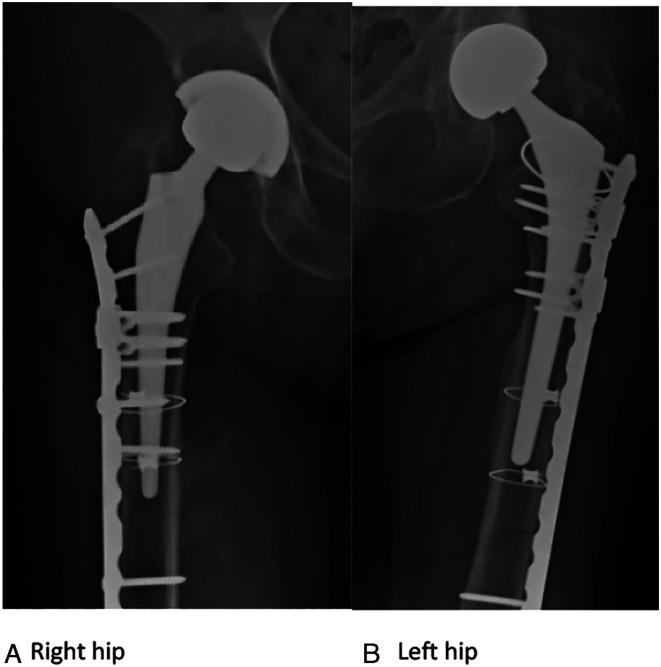

The locking attachment plate (LAP) can be added to a locking compression plate (LCP) to allow the fixation of locking screws bicortically around a femoral implant. We aimed to examine surgical and fracture characteristics associated with healing for periprosthetic femur fractures (PPFFx) treated with constructs employing LAP fixation. We hypothesize that the addition of an LAP provides stable peri-implant fixation.

MATERIALS &METHODS: We retrospectively reviewed a consecutive series of 28 PPFFx surgically treated with LCP-LAP constructs by 4 surgeons from 2015-2020. Fractures were classified and grouped using the Vancouver Classification System and included 12 B1, 2 B2, 11 C fractures, and 3 fractures around other stemmed implants. Primary outcome measures included hardware failure such as screw pullout, broken screws, and plate fracture. Clinical complications including infection, non-union, malunion, and reoperation were recorded.

No LAP failures, screw pullout, or broken screws were observed. Two fractured plates (7.1%) occurred in patients with Vancouver C fracture types. Overall complication rate was 17.9% and included 3 non-unions, 1 deep infection, and 1 implant loosening with painful hardware, each requiring reoperation. Differences were observed between unions and nonunions for total number of screws (12.4 vs 14.7, = .005) and number of locking screws used (8.04 vs 11.3, = .03).

The LAP provides adequate fixation and low failure rates where fixation is required around a well-fixed stem. When failures occur, it is from plate breakage and not due to failure of fixation at the area of plate-stem overlap.